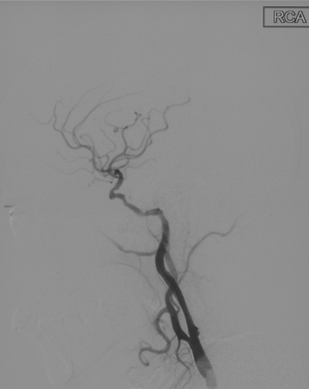

辅助检查(DSA)

R-CA

波科支架怎么样径技-弓上病例大赏|第210期·右侧颈内动脉球囊扩张术+支架植入术_https://www.jmylbn.com_新闻资讯_第12张

• 病例特点:右侧颈内动脉C1段重度狭窄,致远端供血区域脑梗死,手术指征明确;